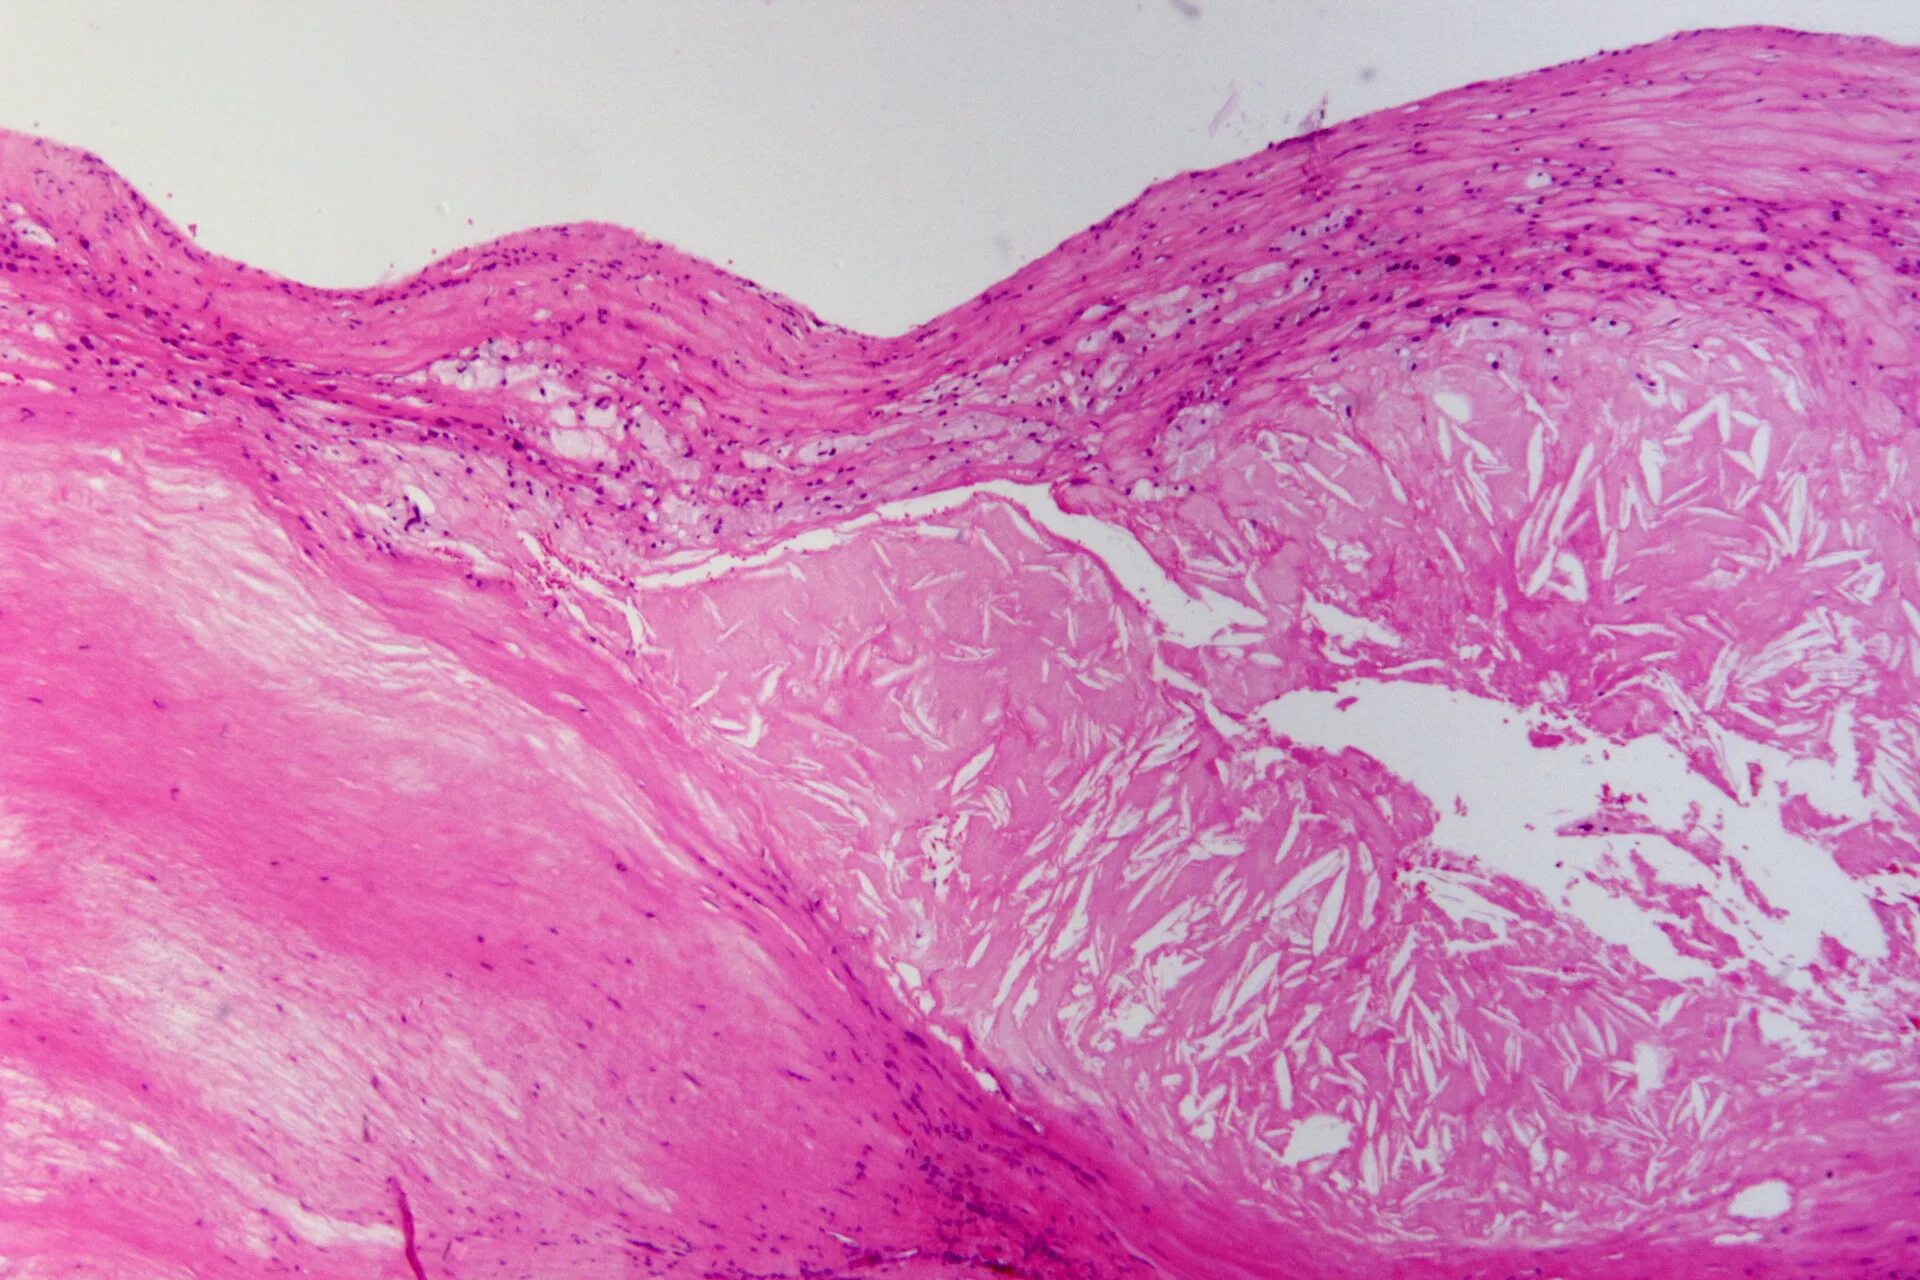

Атеросклероз аорты препарат